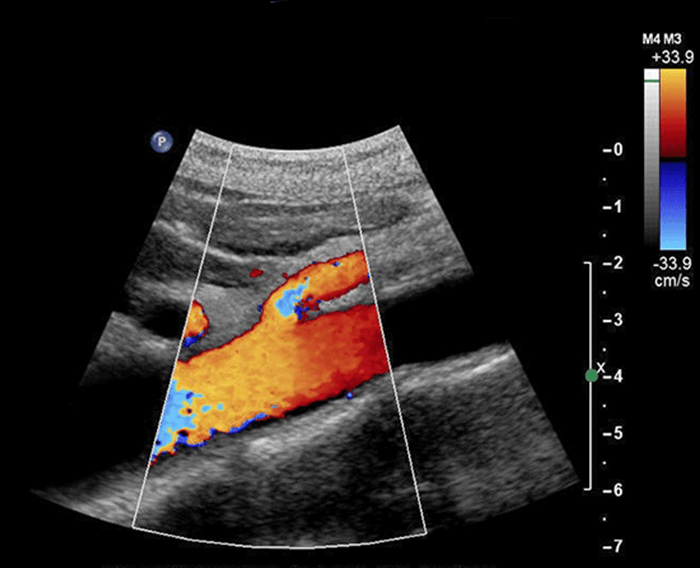

Colour Doppler

A Colour Doppler is a non-invasive, radiation-free ultrasound technique that creates real-time, color-coded images to visualize blood flow velocity and direction within vessels.